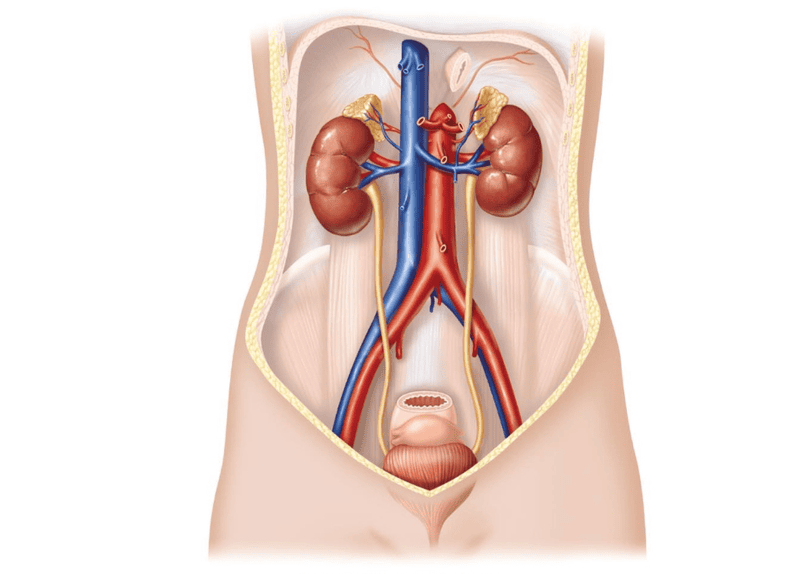

Chụp niệu đồ bài tiết hay X quang hệ tiết niệu bằng đường tĩnh mạch (Intravenous Urography, IVU) còn được gọi là chụp X quang bể thận bằng đường tĩnh mạch (Intravenous Pyelography, IVP) là kỹ thuật sử dụng X quang (tia X) và thuốc cản quang tiêm qua đường tĩnh mạch để giúp khảo sát thận, niệu quản, bàng quang và niệu đạo.

Chụp niệu đồ tĩnh mạch (PIE-uh-low-gram), còn được gọi là hình ảnh niệu đồ bài tiết, là một xét nghiệm chụp X-quang đường tiết niệu của bạn. Chụp niệu đồ tĩnh mạch cho phép bác sĩ xem thận, bàng quang và các ống dẫn nước tiểu từ thận đến bàng quang (niệu quản).

Ở người bình thường, hệ tiết niệu bao gồm các cơ quan như thận, đài-bể thận, niệu quản, bàng quang và niệu đạo. Máu trong hệ tuần hoàn sẽ đến thận để lọc các chất bài tiết tạo ra nước tiểu. Từ đó, nước tiểu sẽ được đi qua ống thận tái hấp thu lại một số chất cần thiết cho cơ thể. Sau đó, nước tiểu sẽ được đổ vào đài-bể thận theo niệu quản đến bàng quang, cuối cùng sẽ được bài xuất qua niệu đạo ra ngoài cơ thể.

Bình thường, các cơ quan này không nhận diện được trên phim X-quang thông thường. Tuy nhiên, với phương pháp chụp niệu đồ bài tiết (niệu đồ tĩnh mạch) bằng cách tiêm thuốc cản quang vào cơ thể, qua quá trình bài tiết chất cản quang mà bác sĩ có thể nhìn rõ được các cấu trúc của hệ tiết niệu trên phim X-quang. Thuốc cản quang có tác dụng năng cản tia X đi qua, do đó cấu trúc của thận, niệu quản và bàng quang sẽ hiện rõ trên phim X-quang, từ đó phát hiện được các cấu trúc bất thường của hệ tiết niệu.

Trong quá trình chụp niệu đồ tĩnh mạch, bạn sẽ được tiêm thuốc cản tia X (dung dịch cản quang i-ốt) vào tĩnh mạch ở cánh tay. Thuốc cản quang chảy vào thận, niệu quản và bàng quang, phác thảo từng cấu trúc này. Hình ảnh X-quang được chụp vào những thời điểm cụ thể trong quá trình khám, vì vậy bác sĩ có thể nhìn thấy rõ đường tiết niệu của bạn và đánh giá nó hoạt động tốt như thế nào.